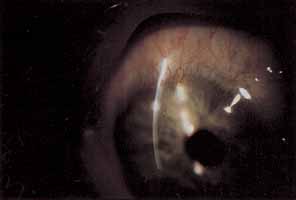

EPITHELIUM The corneal epithelium bears the brunt of mechanical trauma and chemical alterations meted out during contact lens wear. Hypoxia is emerging as a major force in corneal epithelial damage not explainable by direct trauma related to lens defects or handling. Decreasing dK in rigid lenses in an animal model increased the observed degree of corneal epithelial cell swelling and desquamation.78 Extended soft contact lens wear has been implicated in specular microscopic observations of enlarged surface epithelial cells, suggesting a slower turnover of cells under these conditions.79 Even scant concentrations of common contact lens disinfectants, which come into intimate contact with the epithelial surface on a daily basis in hydrogel lens wear, cause epithelial cell retraction and decreased mitotic activity.80 The spectrum of corneal epithelial injury secondary to contact lens wear extends from mild punctate epithelial keratopathy in specific patterns to severe ocular surface disorders with indolent ulceration, anterior stromal scarring, superficial vascularization, and decreased vision requiring surgical intervention.81 There has even been a report of intraepithelial neoplasia associated with contact lens wear in the setting of extensive acute ultraviolet radiation exposure.82 Because isolated trauma to the epithelium may lead to serious corneal scarring, persistent contact lens abuse may lead to visual loss requiring penetrating keratoplasty.83,84 With enough foresight most contact lens wearers may avoid these devastating results. PUNCTATE EPITHELIAL KERATOPATHY Punctate epithelial keratopathy (PEK), or superficial punctate keratitis (SPK) to which it is often incorrectly referred, may result secondary to trauma, hypoxia, drying, chemical toxicity, or any permutation of the previous list.9,85 Discontinuing lens wear, eliminating potentially toxic topical medications, and treating tear surface abnormalities are the mainstays of therapy for these findings. Specific changes in contact lens material, fit, care, or wearing time may be required to prevent recurrence. Contact lens overwear produces a coarse central pattern of staining that is often associated with excessive rigid and soft contact lens wear as well as with flat-fitting rigid lenses.9 The severity of staining is proportional to the duration of contact lens abuse and will determine recovery time following discontinuing lens wear. Discontinuing extended wear, decreasing daily wear time and refitting with steeper rigid lenses are all possible approaches to prevent recurrence.26 The presence of an arcuate patch of PEK near the superior limbus is suggestive of hypoxia secondary to a tight upper lid.9 This may be addressed by refitting with higher dK lenses or decreasing the duration of continuous lens wear. Contact lens-related superior limbic keratoconjunctivitis presents with additional signs and symptoms to accompany the irregular superior PEK that develops in noncontact lens-related SLK.9,74,75 The diagnosis and treatment of this condition have been discussed previously under conjunctival complications. Corneal PEK secondary to solution toxicity commonly presents as a diffuse pattern of superficial punctate fluorescein staining involving the entire corneal surface, often including the limbal conjunctival surface as well.9 Patients complain that the lenses sting immediately upon insertion. Review of lens care protocol is critical to eradicate this complication. Hand washing should be doubly stressed. Dendriform punctate epithelial keratopathy occurs in the setting of severe contact lens solution toxicity or hypersensitivity.9,86–88 These dendriform lesions are slightly raised epithelial plaques that stain lightly with fluorescein (Fig. 2). In contrast, dendrites related to herpes simplex keratitis are intensely staining true ulcers and exhibit terminal bulbs. An association with contact lens solutions preserved with thimerosal and chlorhexidine has been suggested. Lens discontinuation and supportive therapy with nonpreserved tears and ointments constitute effective therapy. Lenses may be reintroduced using nonpreserved saline and thermal disinfection. Significant delay in diagnosis or persistent lens wear, in spite of these findings, may result in permanent stromal scarring beneath the dendriform epitheliopathy. Treatment with antivirals is not helpful and may worsen subsequent subepithelial scarring. Foreign body patterns of epithelial staining are similar to those seen with embedded foreign bodies in the upper tarsal conjunctiva. Contact lenses must be carefully inspected for embedded foreign bodies, tears, or nicks. Trapped debris under the lens is more commonly associated with rigid lens wear and may also cause this staining pattern. This finding may be avoided by attending to cleanliness at the time of lens insertion, avoiding contact lens wear for activities involving airborne foreign material, and controlling the amount of makeup applied to the lid margins. Three and nine o'clock staining occurs commonly with rigid lens wear but may occur with soft lens wear as well.9 Pie-shaped wedges of PEK appear at the nasal and temporal limbus as a result of poor wetting of the local epithelium. Patients with pronounced against-the-rule astigmatism are more susceptible to this type of staining because of the bearing pattern of the lens. Persistent lens wear, in spite of this staining, may result in scarring and rarely pseudopterygia formation.89 Susceptible patients may develop raised scarring consistent with Salzmann's nodular degeneration. Refitting smaller diameter lenses with thinner edge design may eliminate mechanical trauma related to friction from the lens edge. Cases in which astigmatism is contributory may be addressed by using back-toric lens designs or soft-lens piggyback systems. Inferocentral patches of PEK occur secondary to desiccation associated with contact lens- related dry eye or exposure. Supplemental lubrication during lens wear may be required to prevent recurrence. Decreasing wear time or switching to low water content, soft lenses may also improve results. Contact lens wear may be salvaged by permanent punctal occlusion in selected cases of aqueous deficiency dry eye. Topical cyclosporin-A drops (Restasis) may be used to restore enough tear production to allow continued lens wear. Punctate epithelial keratopathy is a common finding often neglected as minor in the grand scheme of complications related to contact lenses. Remember that persistent epithelial staining puts the wearer at risk for microbial keratitis and may, when it progresses to coarse punctate erosions, represent the early stages of pseudomonas or acanthamoeba keratitis.90–92 ABRASIONS Corneal abrasions may be caused by lens defects or may occur during lens insertion or removal. Abrasions occur more frequently with rigid lens wear because lens defects have sharp edges and foreign material gains access to area under the lens more easily.6 Corneal abrasions with soft lens wear are seen most frequently with tight lenses or extended wear lenses. In these situations acute epithelial hypoxia impairs epithelial attachment to Bowman's layer. Treatment is the same as that for noncontact lens-related abrasions. Careful examination of the lens and its fit and queries to the patient regarding techniques of lens removal are important to identify causes of recurrent abrasions. EPITHELIAL EROSIONS Extended wear soft contact lenses are often used as a therapeutic modality for recurrent erosions resistant to medical therapy with topical hypertonic saline. However, animal studies suggest that extended contact lens wear worsens epithelial adhesion.93 This may explain the occasional contact lens intolerance seen with anterior epithelial basement membrane dystrophies.94 The osmotic effects of high water content, ultra-thin soft bandage lenses may counteract the effect of decreased adhesion by dehydrating the epithelium; however, this desiccation may, in turn, promote the formation of coarse punctate erosions in the central and paracentral cornea.9 These erosions are less likely to occur under highly humid conditions. Epithelial erosions related to extended contact lens wear elevate the risk of pseudomonas keratitis and should be treated accordingly.95 MECHANICAL INDENTATIONS There are two distinct types of epithelial wrinkling, both of which are considered benign and non-progressive.9 The first type, called anterior corneal mosaic, may be induced in normal eyes by applying pressure externally or reducing intraocular pressure. This mosaic pattern occurs in association with rigid lenses that have significant central bearing, such as those fit for apical bearing in keratoconus.96 The pattern quickly resolves with removal of the lens but may persist in the presence of abnormally low intraocular pressure. The second type of wrinkling produces criss-crossing furrows on the epithelial surfaces that pool fluorescein.9,97 Extended wear, ultra-thin soft contact lenses are implicated as the cause of these furrows, which are deeper and fade more slowly than those related to rigid lens wear. Corneal wrinkling, also referred to as the “rippling phenomena,” is not associated with progressive changes of the corneal surface and does not necessitate lens removal.97 Air bubbles trapped beneath rigid lenses between blinks will form small indentations in the epithelial surface called dimples.9 Dimpling occurs in PMMA lens wearers most frequently but can rarely be found in soft lens wearers. No treatment is required. Persistent pressure of the edge of a rigid lens may leave an arcuate furrow or ring on the corneal surface.9 This lens edge imprint typically lies inferior in the cornea but may represent the entire lens. Entire lens imprints are more commonly found with PMMA lenses and extended wear, gas-permeable, rigid lenses that adhere to the corneal surface during sleep.37,38 Recurrent lens imprints may result in corneal distortion that over time may become permanent. Further discussion of the implications and treatment of corneal distortions related to contact lens wear will be addressed in the section entitled “Corneal Deformation: Corneal Warpage and Keratoconus.” EPITHELIAL MICROCYSTS Epithelial microcysts form in response to the hypoxia of soft contact lens wear.9,98–100 They appear after 6 to 8 weeks of lens wear and appear as translucent dots that show reversed illumination when viewed in retroillumination. They may be confused with lesions found in Meesmann's epithelial dystrophy but will resolve with proper care. The prevalence and severity are inversely proportional to lens dK and proportional to lens wearing time. Altering either of these parameters in a patient who has developed greater than 50 microcysts or whose cysts begin to stain with fluorescein will cause gradual reduction of the number of microcysts within 3 months. Rarely lens wear must be discontinued. SUPERFICIAL NEOVASCULARIZATION Superficial corneal neovascularization is a response to persistent hypoxia secondary to contact lens wear (Fig. 3).9,101–103 Rigid lenses rarely develop limbal hyperemia greater than normal controls. Daily wear–lens patients will often show an apparent increase in limbal vascularization, which actually represents limbal capillary dilation and rarely progresses to frank neovascularization. Extended-wear soft contact lens wearers most often exhibit significant limbal new vessel growth. Topical nonsteroidal antiinflammatory agents may suppress neovascularization, but their use has not become routine.104 Most often treatment consists of changing from extended to daily wear schedules, fitting with higher dK or thinner lenses or fitting with a looser soft lens. The use of soft extended wear lenses after penetrating keratoplasty is particularly risky because of the rapid neovascular response observed.105 HYPOESTHESIA Corneal hypoesthesia is most commonly associated with PMMA contact lens wear.9,106 This complication explains the blissful ignorance of some more severe complications by the average PMMA lens wearer. Refitting with gas-permeable rigid lenses restores corneal sensitivity of these patients within 2 to 3 weeks.107 Soft contact lens wear has been implicated in corneal hypoesthesia to a degree less than PMMA lens wear, and the hypoesthesia is inversely proportional to the oxygen transmissibility of the lens.9,108 Corneal hypoesthesia contributes to the osmotic effects of contact lens wear by decreasing reflex tear secretion.9 |